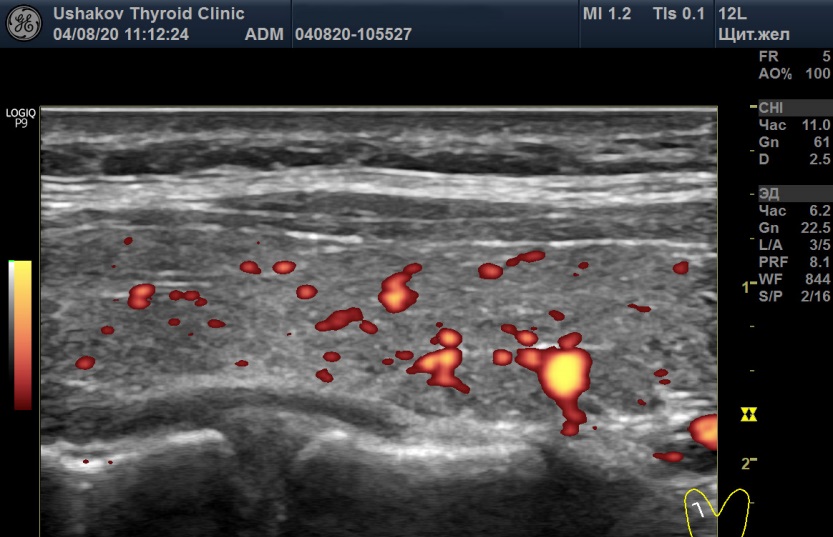

При анализе крови 31.07.20 ТТГ 11,5мМЕ/л [0,4-4,0], Т4св. 9,5 пмоль/л [9,0-19,1], Т3св. 5,3 [2,63-5,7], Т4общ. 74,5 нмоль/л [66,6-150,8], АТ-ТПО 1302 МЕ/мл [<5,6], АТ-ТГ 277 [<10]. Величина антител к рецепторам ТТГ не определялась в связи с гипотиреозом. УЗИ щитовидной железы 04.08.20 показало объем 9,6 мл (6+3,6), признаки умеренного отёка стромы, малые явления мелко-дольковой деструкции, малую лимфоцитарную инфильтрацию, малое усиление кровотока двух долей и ПССК верхних щитовидных артерий 59,9 см/с справа и 40,6 см/с слева (

рис. 6 и 7).

Рисунок 6 Правая доля щитовидной железы (в режиме энергетического допплера) пациентки С., 22 года. А – 04.08.20 в состоянии гипотиреоза и Б – 11.09.20 в состоянии гипертиреоза. Кровоток в каждой доле в разные даты в малой степени усилен, но значимых изменений интенсивности кровотока при этих УЗИ не выявлено.